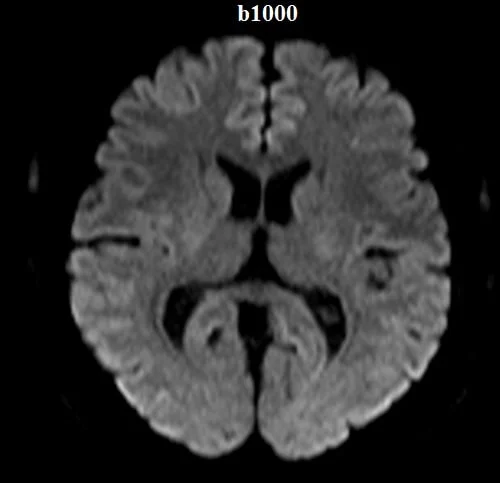

Diffusion-weighted (DWI) axial sequences with b-factors of b0, b500, and b1000 are used in brain imaging.

b-value 1000

DWI (Diffusion-Weighted Imaging) images with b0 and b1000 values in MRI provide distinct information about tissue characteristics.

- b1000 Image: The b1000 image is acquired with higher diffusion weighting, making it more sensitive to water molecule movement. In regions where water diffusion is restricted or hindered, like cellular structures, the signal intensity on the b1000 image may appear hyperintense (bright). This effect is particularly prominent in areas with high cellularity, such as tumors or inflamed tissue, where restricted diffusion leads to elevated signal intensity.

The contrast between the b0 and b1000 images helps identify areas of altered tissue microstructure. Regions with higher signal intensity on the b1000 image compared to the b0 image can indicate restricted diffusion areas, potentially signifying pathology. This information is particularly valuable in fields like neurology and oncology, where DWI images assist in identifying conditions such as tumors, strokes, and hemorrhages based on tissue diffusion properties.